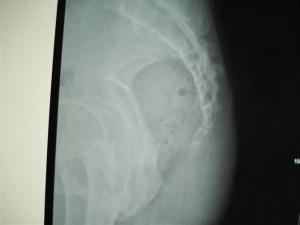

临床上多见,尤其好发于臀部着地跌倒后,女性中的发生率明显高于男性。由骶5,尾1及部分骶3、4神经前支所组成的尾丛神经多与椎旁交感神经干下方纤维相吻合。其分支如下: 1、肌支:分布至肛提肌处。 2、感觉支:有3~5支细小的肛尾神经分布于尾骨区及肛周皮肤。[1]